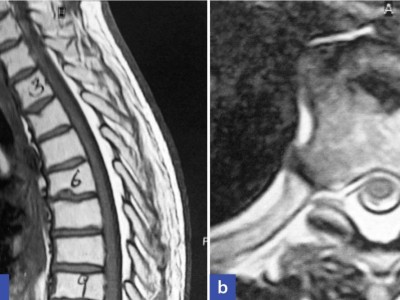

Ein 48-jähriger Patient berichtet von belastungsabhängigen Schmerzen in den Beinen seit mittlerweile zehn Jahren. Bildgebende Untersuchungen der Hals- und Lendenwirbelsäule konnten die claudicatioartigen Beschwerden bislang nicht erklären. Eine lange überfällige MRT des Thorakalbereichs führt schließlich zur richtigen Diagnose.

Chilaiditi-Syndrom in einer CT-Aufnahme/© Peters F & Ritz J-P/ all rights reserved Springer Medizin Verlag GmbH, Initial potenziell instabile Läsion von BWK 10 bei Multiplem Myelom/© Kaufmann, J., Schmidberger, H. / all rights reserved Springer Medizin Verlag GmbH, Springer Medizin Podcast - Endometriose/© (M) Willer D. et al. / all rights reserved Springer Medizin Verlag GmbH Logo: Springer Medizin Verlag GmbH, Zentrale Lungenembolie/© Springer Verlag Berlin Heidelberg 2015, Volumetrie des Bulbus olfactorius/© Keweloh S.. et al. doi.org/10.1007/s00106-025-01650-z unter CC-BY 4.0, Gebrochener Fuß im Gips/© Aleksandr Kirillov / stock.adobe.com (Symbolbild mit Fotomodell), CT-Pulmonalisangiographie/© Das M et al. doi.org/10.1007/s00117-016-0100-3 unter CC-BY 4.0, Kanüle für Katheterbehandlung/© romaset / stock.adobe.com, Komplexe, offene Fraktur des Ellenbogens vom Grad 2/© Springer Medizin Verlag GmbH, Mann erhält einen CT-Scan /© Mark Kostich / stock.adobe.com (Symbolbild mit Fotomodell), Verschlussazoospermie bei unilateraler zystischer Alteration der Samenblase und kontralateraler Samenblasenagenesie/© Wittler C et al, Indikationen zur konventionellen Bildgebung am Ellenbogen/© Rentschler V et al. / all rights reserved Springer Medizin Verlag GmbH, Person schenkt Bier in Kolben/© Parilov / Stock.adobe.com (Symbolbild mit Fotomodell), Neoadjuvanten Strahlentherapie bei Liposarkom/© Podleska, L.E. et al. / all rights reserved Springer Medizin Verlag GmbH, Frau erhält eine Strahlentherapie/© Mark Kostich / stock.adobe.com (Symbolbild mit Fotomodell), Schaumiges Bronchialsekret bei akutem Lungenödem/© Eichner M. doi.org/10.1007/s00063-025-01258-9 unter CC-BY 4.0, Bildgebung bei akuter Organblutung/© Nadjiri J / all rights reserved Springer Medizin Verlag GmbH, Bildgebung bei Beckenfraktur mit Blutung der A. iliaca interna/© Fink CB et al. / all rights reserved Springer Medizin Verlag GmbH, Traumatische Aortenverletzung/© Maier J et al. / all rights reserved Springer Medizin Verlag GmbH, Oberbauchsonoraphie/© C. Raschka, Muzinöses Prostatakarzinom/© Garzaro JRR et al. / all rights reserved Springer Medizin Verlag GmbH, Intraspinales thorakales Lipom/© Andreas Frank / all rights reserved Springer Medizin Verlag GmbH, Frau bei Strahlentherapie/© (M) Mark Kostich / Stock.adobe.com (Symbolbild mit Fotomodellen), Search Icon, Frau hält sich eine Brustseite nach Mastektomie/© chotiga / Stock.adobe.com (Symbolbild mit Fotomodell), Radiologin richtet Mammographiescreening ein/© LIGHTFIELD STUDIOS / stock.adobe.com (Symbolbild mit Fotomodellen)